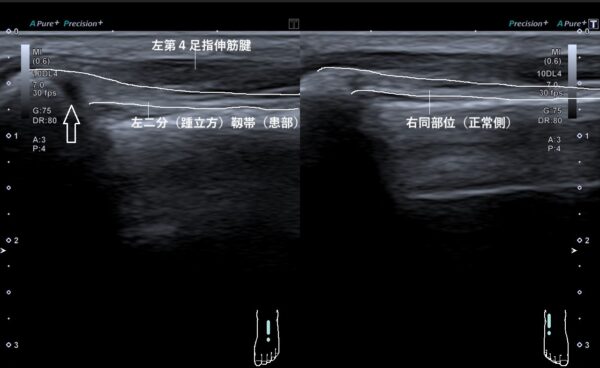

それらの所見から、超音波(エコー)画像観察をしてみると二分(踵立方)靱帯が部分断裂していました(画像、矢印の先の黒い箇所が断裂および出血箇所)。

踵立方靱帯は踵骨と立方骨の足根骨をつなぐ靱帯で、歩行やバランスを保持する役目をしています。